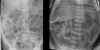

What is Hirschsprung’s Disease?

This disorder is characterized by the absence of particular nerve cells (ganglions) in a segment of the bowel in an infant. The absence of ganglion cells causes the muscles in the bowels to lose their ability to move stool through the intestine (peristalsis).

What does Hirschsprung’s Disease involve?

• HD involves agangliosis of both plexuses in distal colon & rectum

SO the absent/damage to the ganglia here means that the nerves are not funcitonal = muscle atrophy/wastage